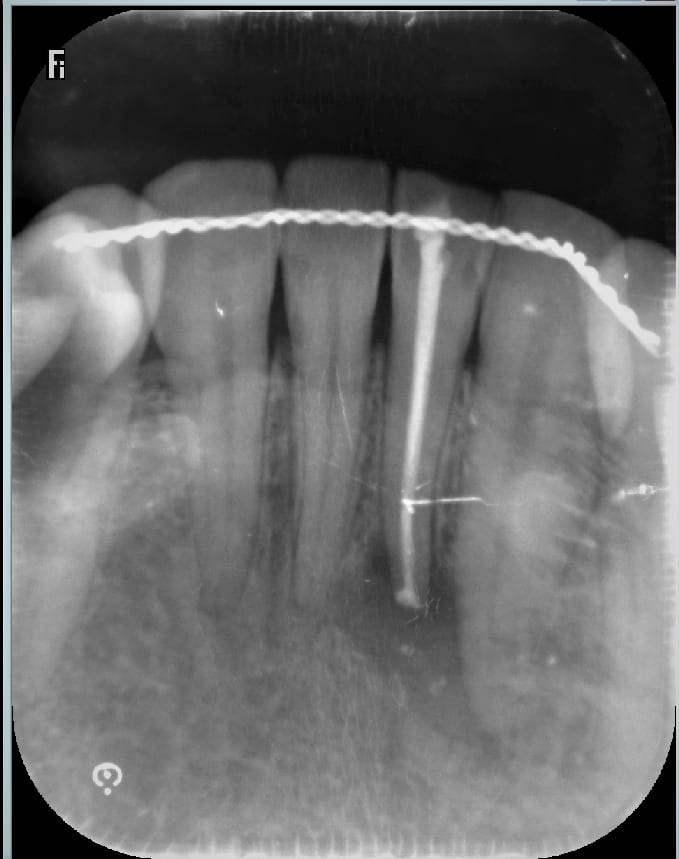

- acte 1 la dent est necrosée , asymptomatique , et lors d un contrôle det , une radio est prise . suite à une image à l apex , l' endo est faite , . , sans anesthesie . ok .

le résultat radio est plutôt sympa .

verifie par des inicidences variées l'existence d'un 2e canal

Pour le froid t'es sur c'est la latérale qui fait mal et pas la canine dont l'apex est très proche de la lésion apicale ?

Et puis cette contention....

1) il n'y a pas de deuxième canal.